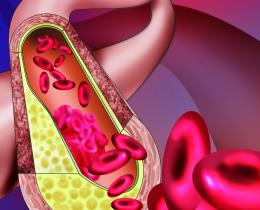

„Möglichkeiten der Diagnostik und Therapie aus gefäßchirurgischer Sicht“

„Interventionelle Therapiemöglichkeiten zur Regulierung des Blutflusses!“